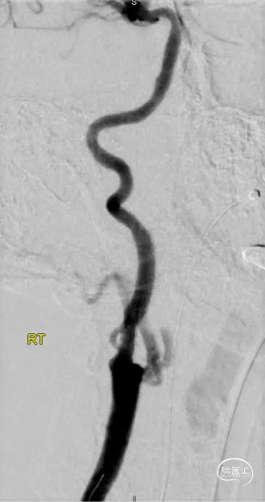

手术过程和决策:标准TCAR入路,右侧颈动脉血管造影多角度显示右侧ICA起始部99%狭窄(图3)。通过病变后,选择了一种改良的快交导管来验证管腔位置。由于Enroute导丝较短,通过截断快交导管的近端并将造影导管连接到远端导管进行造影剂注射。这使我们能够验证我们穿过病变后是否在真腔内(图4)。病变用6*40mm Viatrac球囊进行扩张,随后使用8*30mm Enroute自膨支架从ICA释放至颈动脉分叉上方,然后使用9*30mm Enroute自膨支架治疗CCA。血管造影显示无明显狭窄,ICA未闭(图5)。

图3. 颈动脉造影显示右侧颈总动脉(CCA)未闭,颈内动脉(ICA)起源狭窄99%。